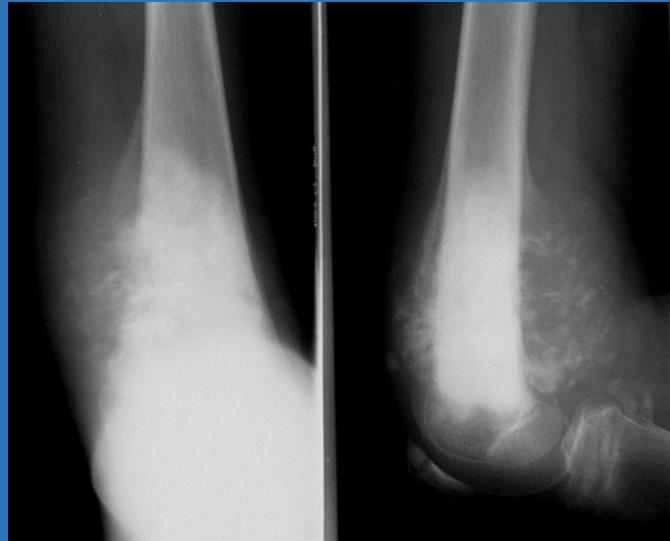

Injection for Tennis elbow (Lateral Epicondylitis)

This patient has lateral epicondylitis. You are required to give him an injection

![]() |

Injection for golfer elbow (medial epicondylitis)

https://www.youtube.com/watch?v=eVaguVc53DM&pp=ygUfSW5qZWN0aW9uIGZvciBnb2xmZXIgZWxib3cgb3NjZQ%3D%3D

This patient has medial epicondylitis that has not responded to conservative management. You are required to inject the site with steroid and local anesthetic agent.

Tennis Elbow (Lateral Epicondylitis)

Have you ever heard of tennis elbow or suffered from elbow pain? Continue reading to learn about this condition and a new study that may change the way we approach treating this problem.

Steroid injection for tennis elbow

INJECTION TARGET Therapeutic agent is injected between the bone and the common extensor tendon (about 1 cm anterior to the lateral epicondyle with the elbow in a flexed position)

Golfer’s Elbow (Medial Epicondylitis)

Pain occurs on the inside part of the elbow where the tendons of the forearm connect to the medial epicondyle. Pain may spread down the forearm to the wrist.